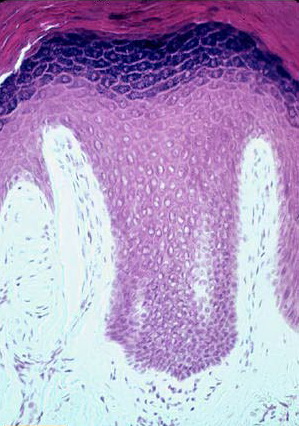

Section of thick skin = مقطع في جلد سميك